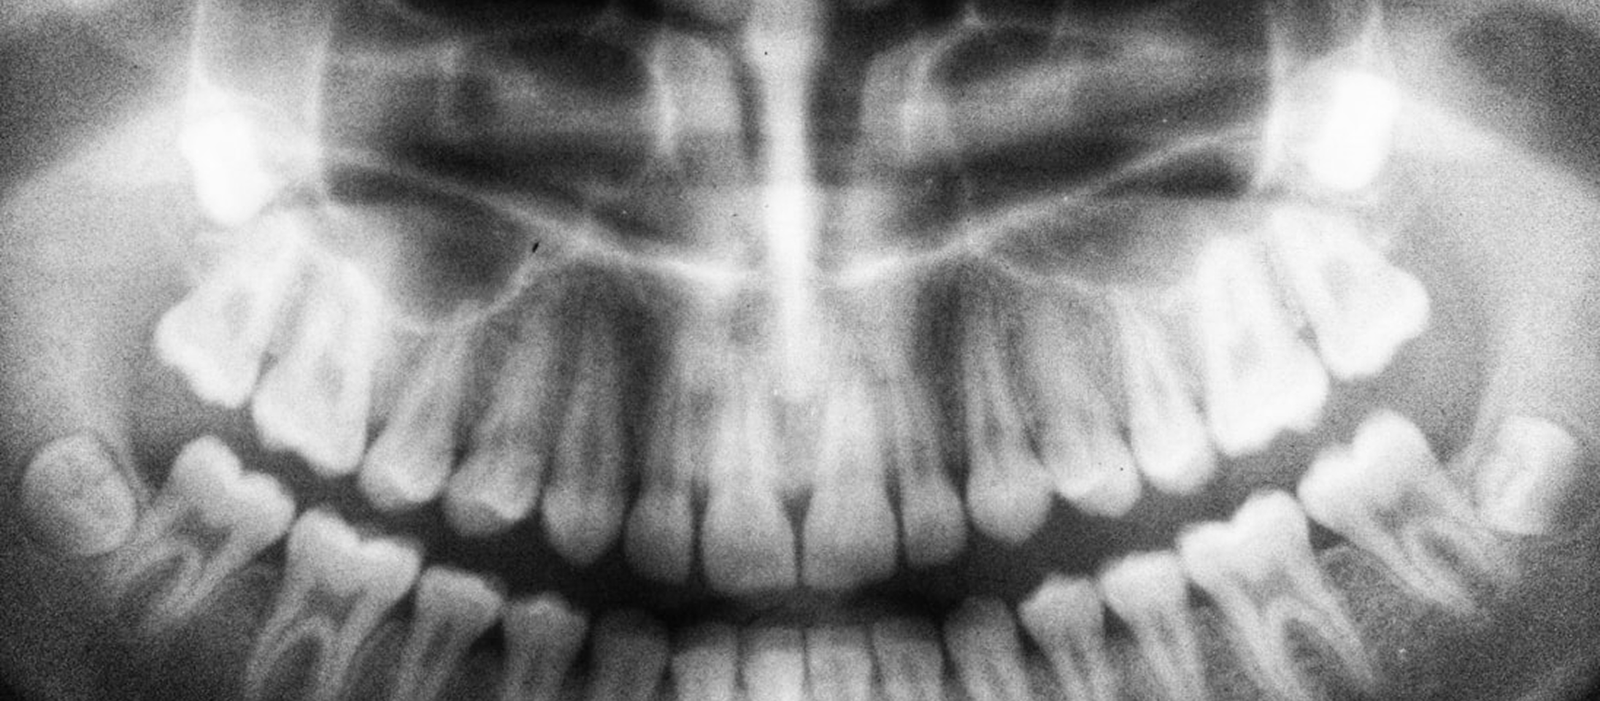

Se dedica al diagnóstico y tratamiento de las enfermedades de la cavidad oral.